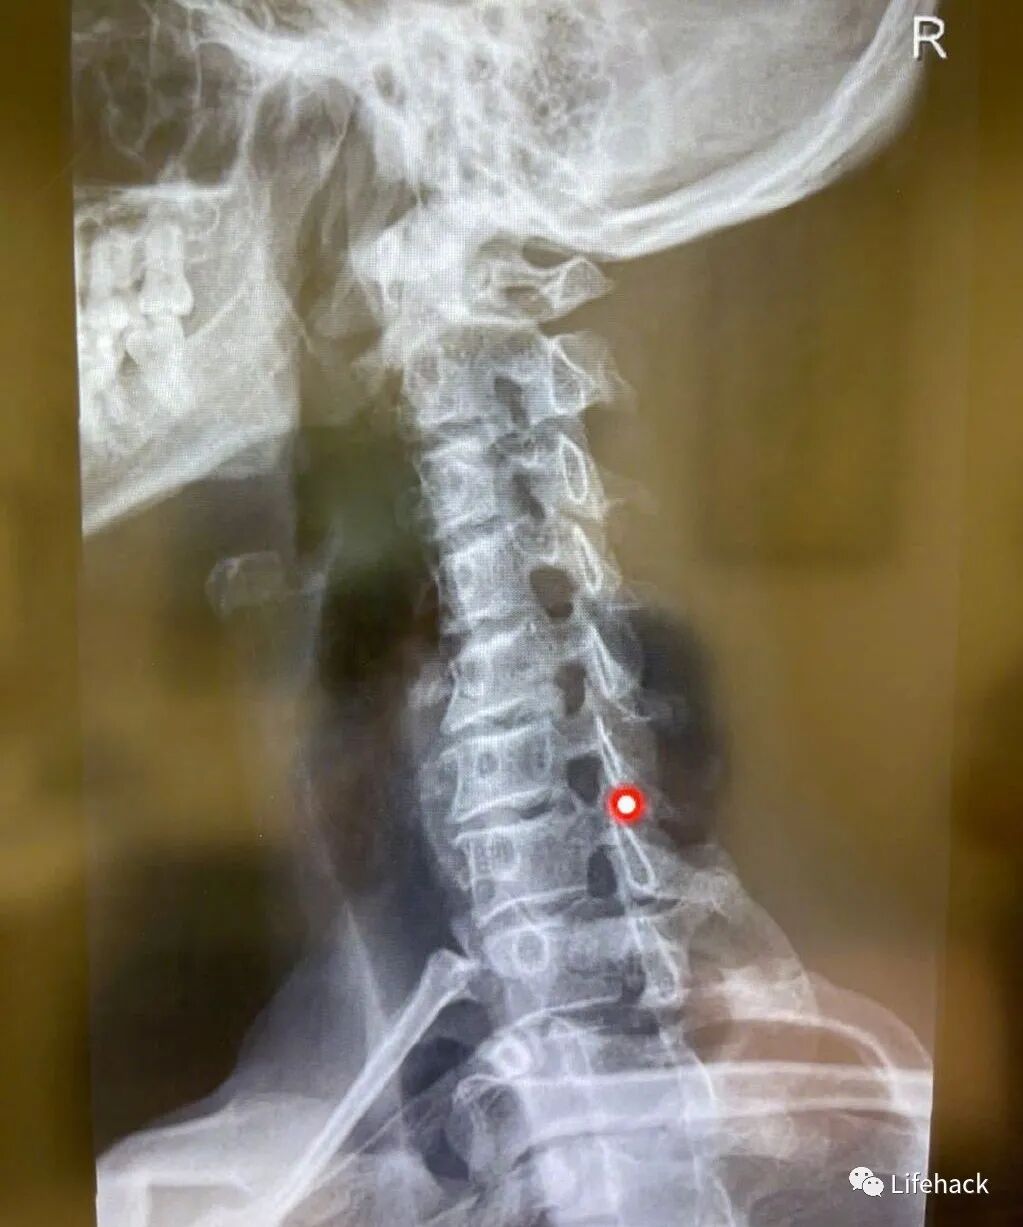

看到粉丝们对他的颈椎如此好奇,李治廷在下午还专门对此发了一条微博,调侃说要给大家演奏一首《我的颈椎》,并配上了两张他的颈椎CT片子。

片子中红点的位置应该就是他颈椎出问题的地方,简单直观地不难看出,这个位置就是长期保持低头姿势时,颈椎受压最大的位置所在!